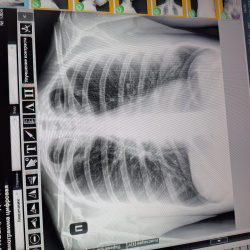

Ж 1967 г.р Жалуется на боль на уровне 9 и 10 ребер слева, боль беспокоит 4 дня, травм не было. поднимала контейнер весом 10 кг; начало болеть после этого. Деструкция и перелом 10 ребра слева?